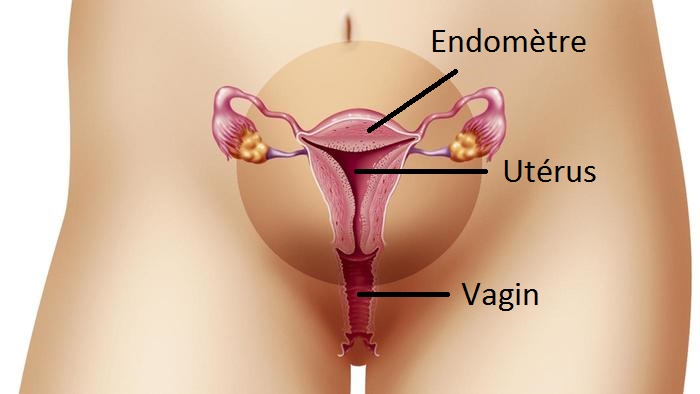

La radiopelvimétrie est un examen qui permet de connaître la mensuration du bassin de la femme enceinte. Ces dimensions permettent de s’assurer que le bassin est suffisamment large pour laisser passer le bébé au moment de l’accouchement.

La radiopelvimétrie est importante car il s’agit d’une radio très précise qui permet de mesurer au millimètre près les dimensions de votre bassin. Et ce, afin de pouvoir les comparer avec celles de la tête de votre bébé. Celle-ci peut être prescrite lorsque l’examen gynécologique qui permet d’évaluer la taille et la forme de votre bassin (réalisé autour de la 37ème semaine) n’est pas suffisamment convaincant.

De plus, si votre bébé se présente en siège, cette radio permet de s’assurer que la tête de votre bébé passera une fois le reste du corps dehors. Car, à ce stade, une césarienne ne pourra plus être pratiquée. Votre médecin vérifie également que vous n’avez pas gardé de séquelles et que votre bassin ne s’est pas déformé suite à un accident par exemple (voiture, scooter …).

La radiopelvimétrie s’avère également être indispensable si vous avez déjà subi une césarienne au cours d’une grossesse précédente. (Bassin déjà trop étroit durant le travail).